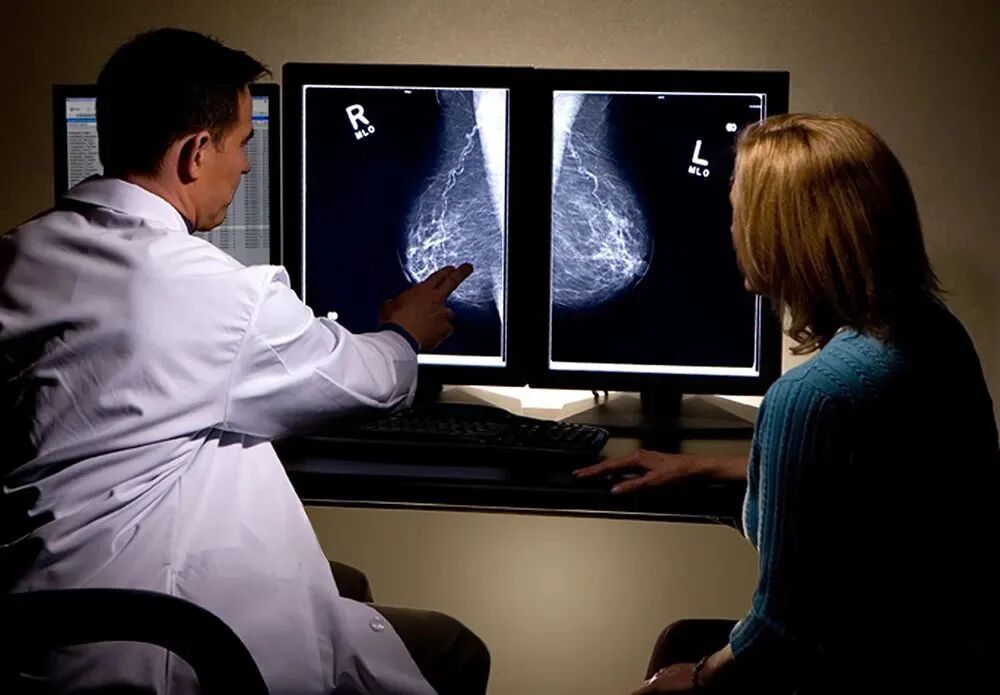

刘女士在2016年因左乳出现肿块,遂前往医院检查,后经过一系列检查确诊左乳乳腺癌,同年3月刘女士接收了左侧乳房切除术和淋巴结清扫术,手术后,她接受了三个疗程的化疗 (CMF)。

本以为经过手术和化疗能够将肿瘤彻底扼杀,但在6月份复查时发现左腋窝淋巴结复发,随后安排了手术切除,在 15 个切除的淋巴结中,11 个发生转移,ER(-)、PgR(-) 和 Hercept 测试为 3+。之后对腋窝进行 50 Gy 放射治疗。

但事情远远没有结束,同年11月复查发现左锁骨上淋巴结肿大,诊断为转移复发,开始2周一次曲妥珠单抗给药。之后刘女士一直保持治疗,一直到2017年5月6日,触诊时锁骨上淋巴结不再触及,超声检查直径缩小至 3 mm。

然而,2018年1月腹部CT发现肝脏多发转移。肝内可见多个低回声结节,边界清晰,周边可见低回声晕,大者位于右叶,另于肝右叶可见片状低回声,余肝实质回声致密,血管显示清晰,走行正常。

由于癌症反复发作让刘女士失去信心,通过血液检测,CEA 和 CA15-3 分别升高到 11.2ng/ml 和 77.2U/ml。为了寻求更好的治疗,刘女士决定尝试细胞免疫疗法,在经过专家面诊以及免疫细胞检查后,专家为其制定了曲妥珠单抗+NK细胞免疫疗法。

自1月23日开始每周一次 PTX(80 mg/m2),2月9日专家提取刘女士血液中的单核细胞,通过2周时间的实验室培养,将其制成“定制型免疫疫苗”后,以静脉注射的方式回输到体内,整个治疗过程刘女士不仅没有出现不适,反而能够清晰感觉到身体状态逐渐恢复。

治疗2个月后,通过CT检查发现肝转移处于部分缓解状态。